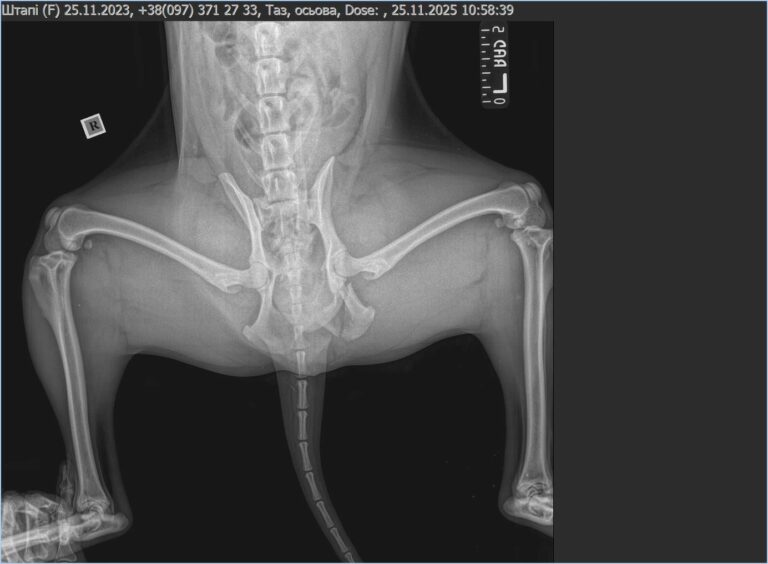

Kilka dni temu, podczas wykonywania obowiązków, Sztapik uległ poważnemu wypadkowi. Żołnierze natychmiast przewieźli go do kliniki, gdzie wykryto uszkodzenia narządów wewnętrznych, złamaną kość miednicy oraz złamaną przednią łapę. Jego stan był krytyczny, ale udało się go ustabilizować i uśmierzyć najostrzejszy ból.

Teraz przed nim długi proces leczenia. Potrzebna jest skomplikowana operacja, pełna diagnostyka, USG, badania kontrolne i stała obserwacja, bo przy takich obrażeniach każdy dzień może przynieść nowe komplikacje. Po zabiegu rozpocznie się rehabilitacja, która może potrwać wiele tygodni lub nawet miesięcy. Sztapik będzie uczył się chodzić od nowa, a jego ciało będzie wymagało systematycznego odciążania, ćwiczeń i specjalistycznej opieki.